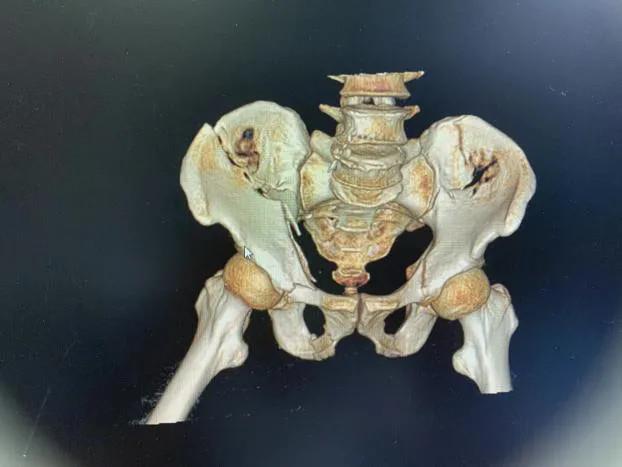

术前影像资料

术后影像资料

拆除内固定后影像资料